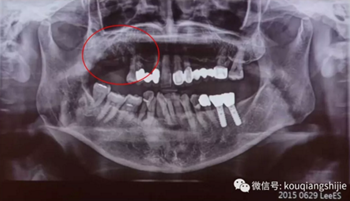

這個(gè)患者是在別的醫(yī)院拔牙后1個(gè)月來(lái)到我們醫(yī)院

我們從CT上可以看到#16,17的拔牙創(chuàng)破壞非常嚴(yán)重

但是因?yàn)槭莿偘窝?個(gè)月,所以我覺(jué)得這個(gè)拔牙創(chuàng)應(yīng)該可以愈合

我們?cè)俣嗟攘?個(gè)月

3個(gè)月后我們發(fā)現(xiàn)缺損部位的黏膜愈合的非常不規(guī)則

翻瓣后發(fā)現(xiàn)也沒(méi)有完全形成骨質(zhì)。